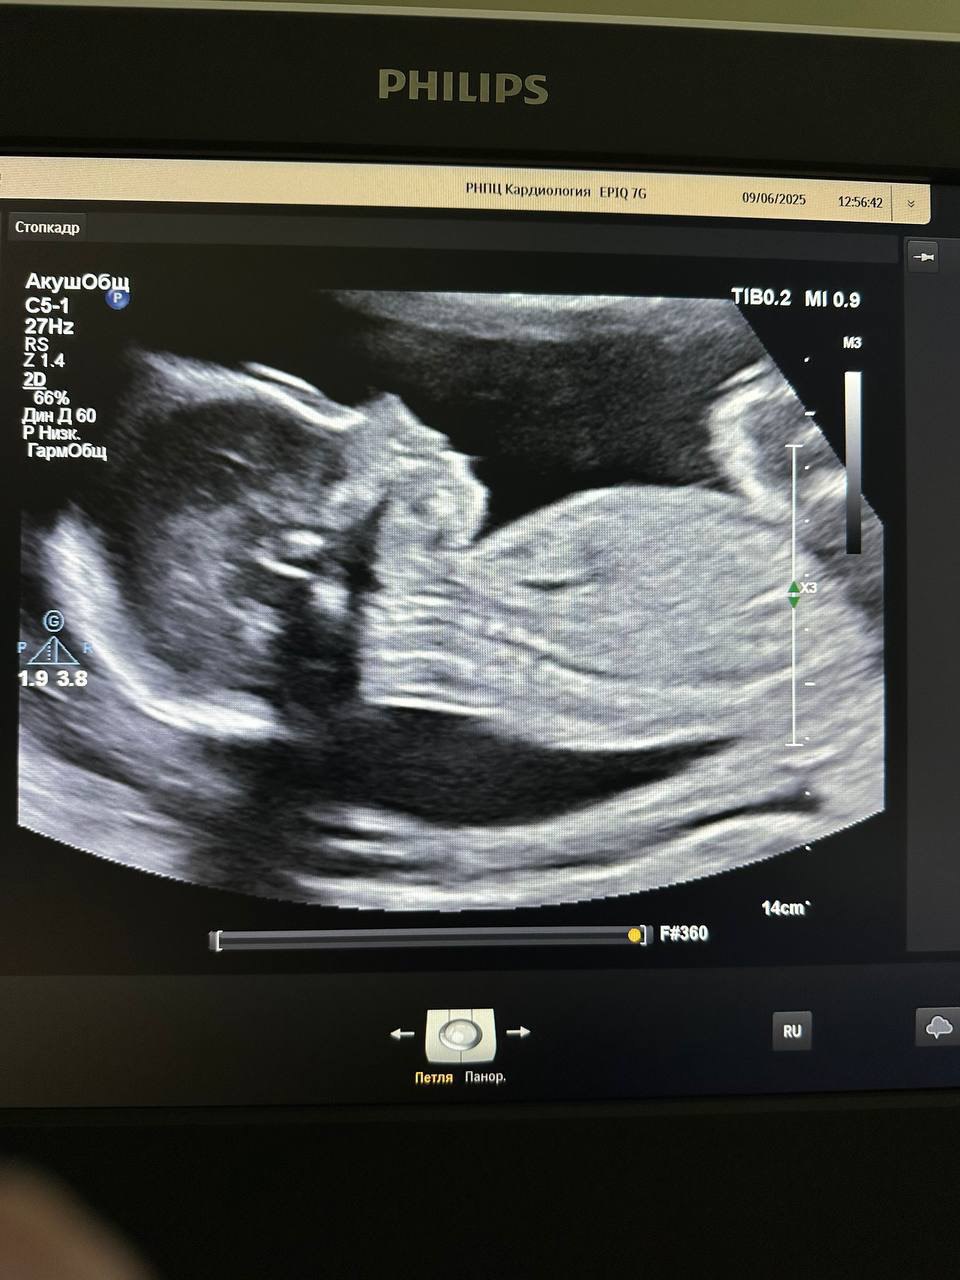

Впервые в Республике Беларусь 02.06.2025 в РНПЦ «Кардиология» проведено высокотехнологичное кардиохирургическое вмешательство пациентке 33 лет на сроке беременности 23 недели — удаление миксомы левого предсердия в условиях искусственного кровообращения.

Слаженная работа мультидисциплинарной команды из специалистов РНПЦ «Кардиология» и РНПЦ «Мать и дитя» позволила блестяще справиться со сложной задачей: устранение жизнеугрожающей ситуации для матери, не навредив при этом развивающейся жизни ребёнка. Операция и послеоперационный период прошли без осложнений. Беременность удалось пролонгировать до 38 недель.

02.10.2025 в результате планового кесарева сечения родился доношенный мальчик массой 3230г, ростом 52 см и с удовлетворительными показателями по шкале Апгар.